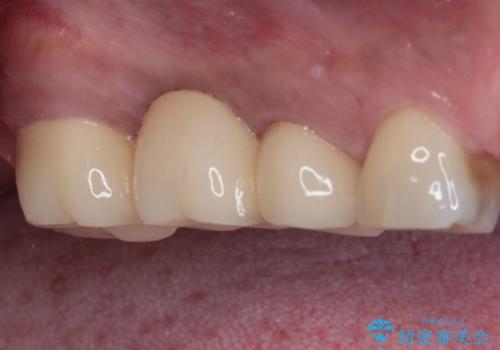

ブリッジ除去後痛みが引いたことを確認し、オールセラミックブリッジによる補綴治療を行うこととしました。

銀歯に隠れていて術前のレントゲンでははっきりと分かりませんでしたが、元々非常に大きなむし歯があったようで、銀歯の中で神経組織が壊死を起こしていました。

速やかに根管治療を行い、無事に痛みを取り除くことができました。